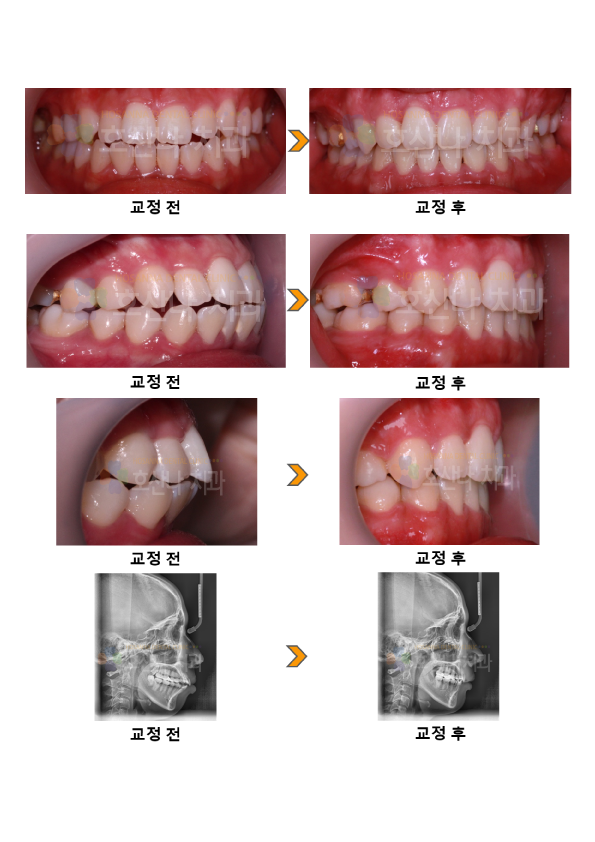

교정비수술 돌출입교정 시술 증례

< 비수술 돌출입교정 시술증례 >

20대 female 돌출입 / 무턱

입이 나왔어요.

환자분은  심한 돌출감을 개선 하기 위해 내원 하셨습니다.

아래턱이 작은 무턱과 뻐드러진 치아각도로 인해 입술이 다물어지지 않고 심미적이지 않은 정면, 측면을 보였습니다.

환자분의 경우 수술 없이 최대한의 돌출을 해소하기 원하셨기 때문에 발치만으로는 그 목표를 달성할 수 없어 미니스크류를 식립하여

원하는 만큼의 돌출을 해소하였습니다.  교정 후 수술 없이 현저한 돌출 개선으로 심미적인 결과를 얻었습니다.

4.교정기간

1y 11m